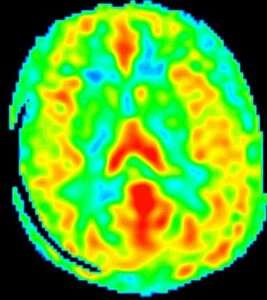

ASL(arterial spin labeling)法とは、脳の血流状態を評価する方法で、図のように描かれます。1) 2)

赤い部分が血流の多い場所を表します。

従来、脳血流の評価というと、放射線核種を用いる脳血流シンチグラフィー(SPECTやPETなど)や、造影剤を用いる検査でしたが、放射線の体内被曝や造影剤による身体的負荷の問題があり、大がかりな設備が必要でした。

MRI装置の高性能化、高磁場強度(3.0T)の装置の登場により、放射線被曝や侵襲のない検査が可能となりました。